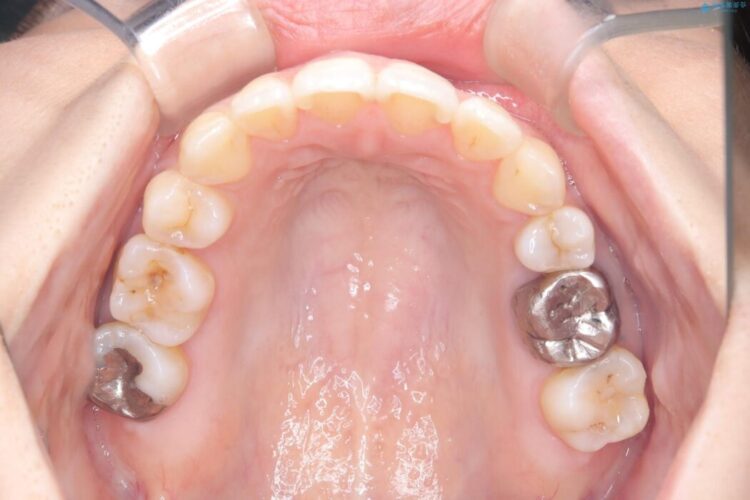

口元を下げて前突感を無くしたい、下の歯の凹凸も無くしたいとご来院された患者様です。

アゴの骨格的なズレがあったため、歯の真ん中を完全に合わせることは不可能と説明。上下4本抜歯を行い、ワイヤー矯正で噛み合わせの大きな改善を目指しました。